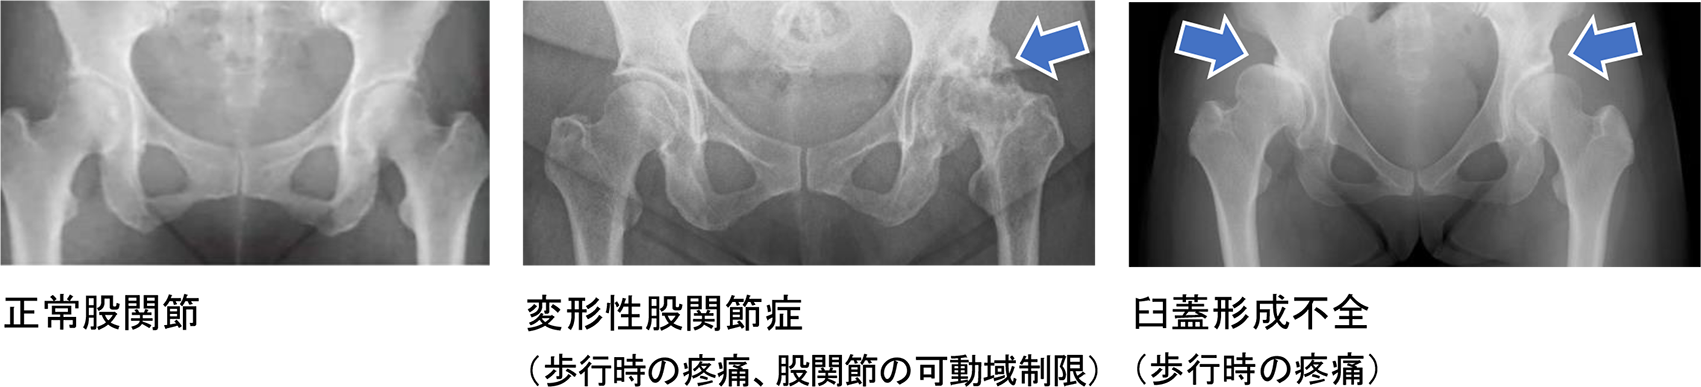

【どんな疾患?】 |

【どんな症状?】 |

【原因は?】